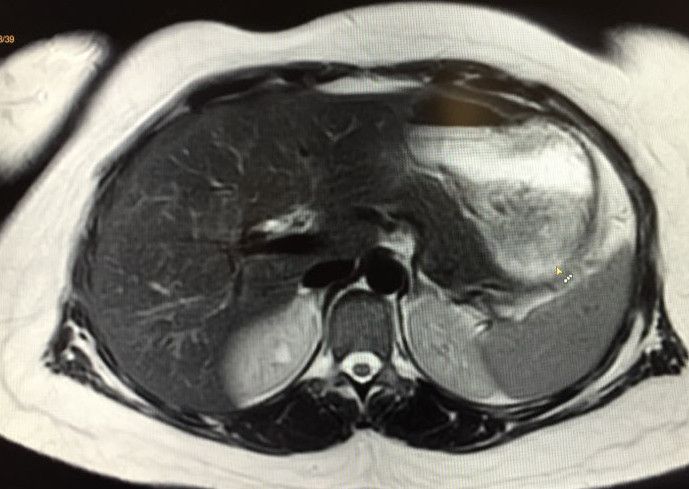

Considérée comme l'une des techniques de pointe en matière d'imagerie médicale, l'IRM ( imagerie par résonnance magnétique) permet souvent un diagnostic précis pour bon nombre de pathologies.

En associant le magnétisme et des ondes radio-fréquences, l'IRM permet de réaliser des images très précises.

Pratiquement toutes les indications, l'IRM est notamment l'examen de prédilection pour toutes études neurologiques.